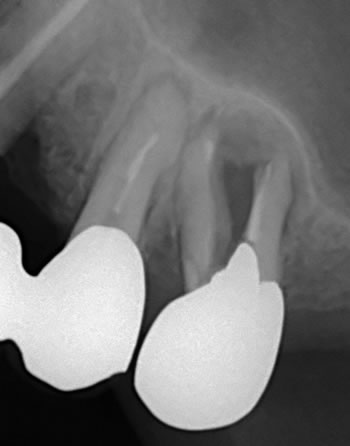

これは別のケースの写真ですが、イメージ的にはこんな感じでした!

歯の根の治療(神経を取る)をすると、歯は割れやすくなる!

根の治療をした歯では硬いものは咬まないように注意する!

根の治療した歯はしみたりの痛みを感じ無くなり虫歯に気付き難くなる!

根の治療した歯があるならば歯の定期検診も必要になってきます! |